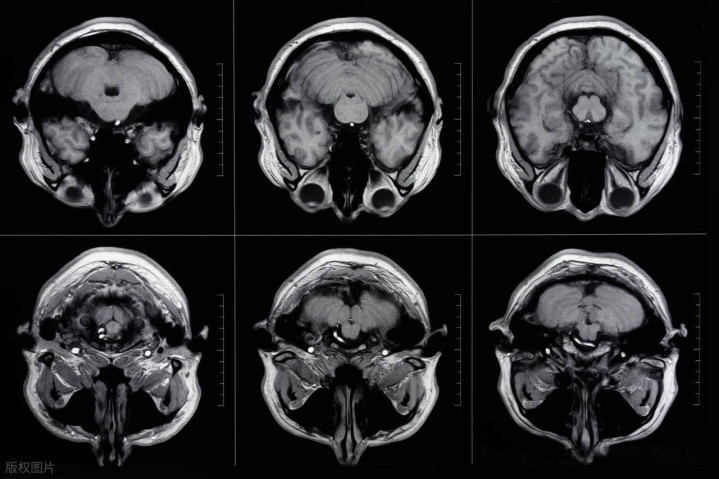

腔隙性脑梗死是一种常见的缺血性脑血管疾病,其是指发生于大脑深部白质、基底节、丘脑等部位的,何况直径不息为0.2-15mm的病灶。临床上凭证病灶数目和散布范围的不同,腔隙性脑梗死可分为单发性、多发性和腔隙景色三种类型,其中多发性腔隙性脑梗死每每教导病情更为严重,对融会功能和生涯质料的影响也更大。